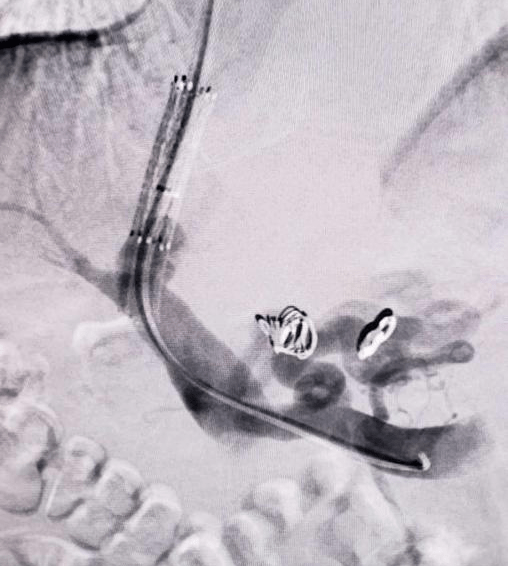

经颈静脉穿刺肝内门静脉分流术(tips)治疗消化道出血_门静脉高压症_门